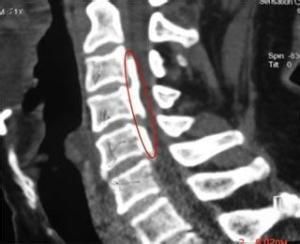

2.CT掃描

對骨結構的顯示比MRI更清晰,不僅可發現骨折、脫位,並可顯示椎管腔變形和脊髓受壓現象。

3.MRI檢查

對脊髓和椎間盤的顯示優於CT檢查,矢狀面能直接觀察到脊髓損傷的範圍和程度以及有無椎管內血腫等。特別是慢性脊髓損傷,明顯優於CT掃描。